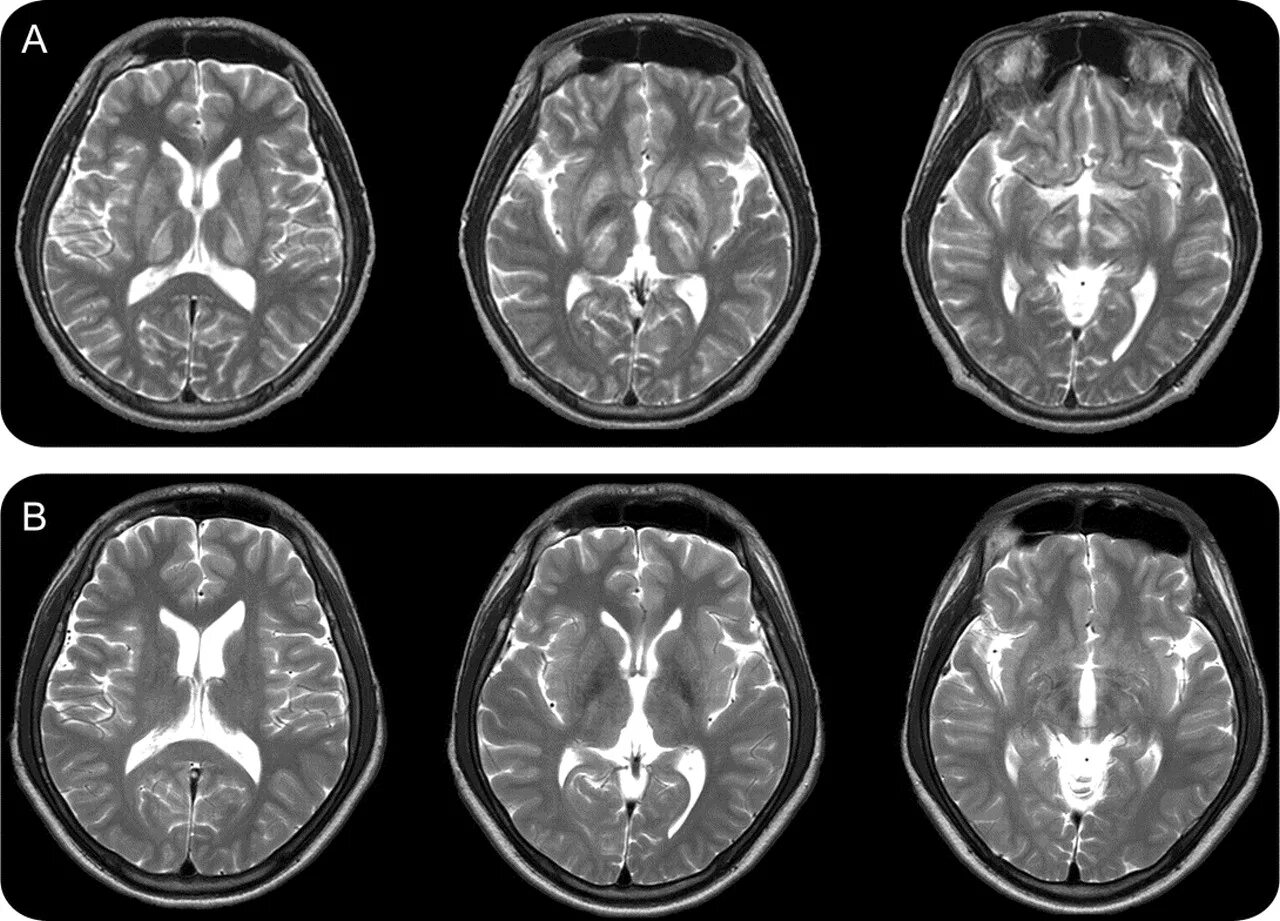

После мрт головного мозга